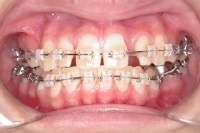

• 上顎の内側に装置

上顎の外側にセラミックブラケットを装着

下顎の奥歯にバンドを装着

• 下顎の外側にセラミックブラケットを装着